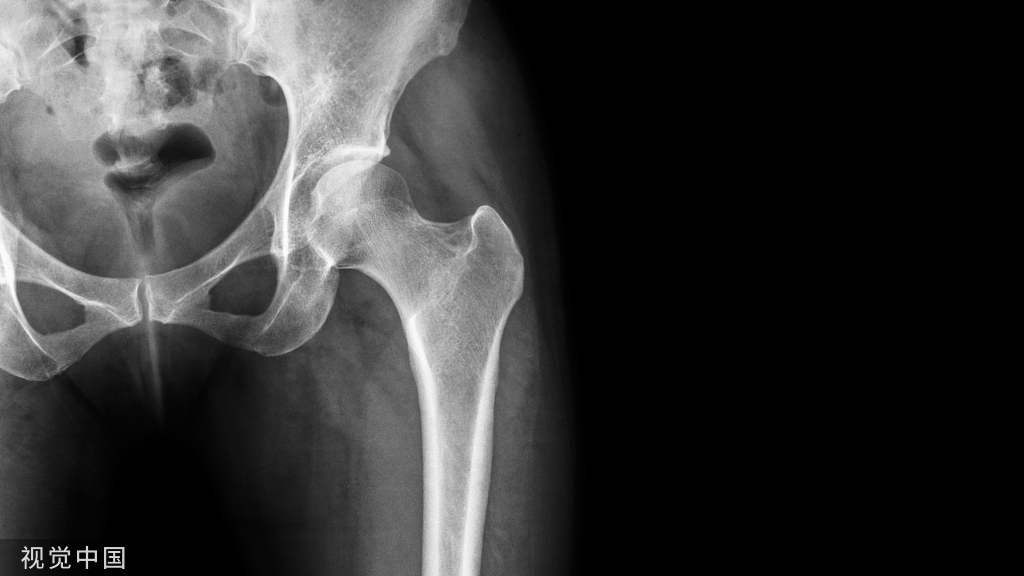

肩胛骨骨折在创伤骨科较少见,约占到全身骨折的0.5%-1%,但近90%存在合并伤。常发生于多发伤患者,多由严重暴力引起。今天就为大家介绍一下肩胛骨骨折的内固定手术技巧!

但3%-5%涉及肩胛带,10%涉及肱骨盂骨折,同时需要注意排除肩锁关节脱位和胸锁关节脱位!